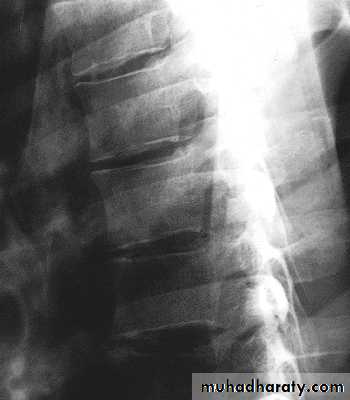

Thoracic Spine X Ray

Lateral radiograph

A/P radiographIn general a typical vertebra consists of :